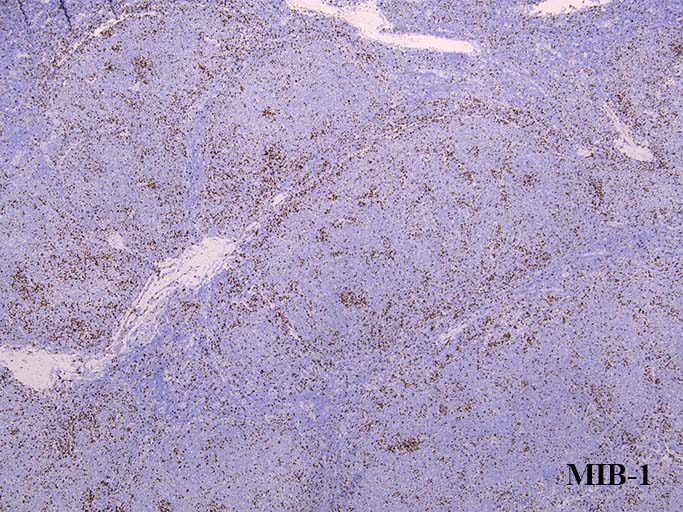

prototypeと同様濾胞内細胞のMIB-1 LIは低値をしめしているようである. (陽性はT-cell)

BCL6は陽性コントロールと比較しても同程度に陽性を示している。初発のdiffuse lymphoma cellのように弱陽性ではない. MIB-1陽性細胞が集簇して認められる. labeling indexは濾胞全体では低値である.

47,idem,-16,+mar2のクローンの染色体が細く、増殖が速いと考えられる. MIB-1+の集簇する細胞と関連している?